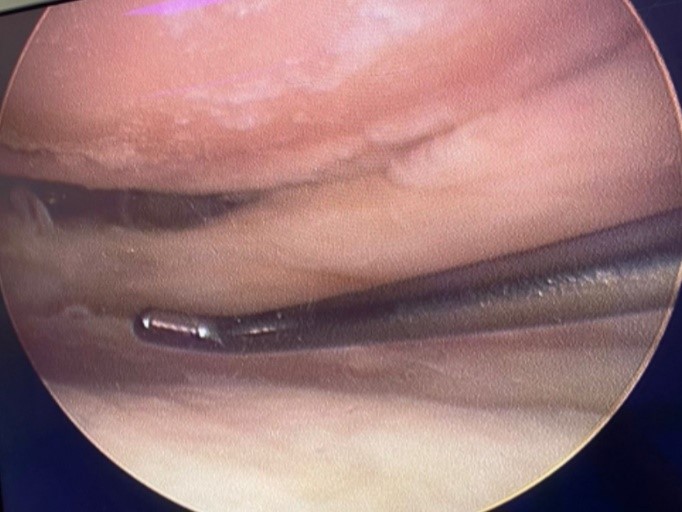

En todos los pacientes se practicó una artroscopia de rodilla (Fig. 1) antes de la osteotomía proximal de tibia para poder evaluar el cartílago del compartimento medial y lateral, así como la existencia de lesiones meniscales asociadas. Las lesiones del cartílago articular fueron estratificadas según la clasificación de Outerbridge17. En caso de lesiones de cartílago de gran extensión, se hicieron nanofracturas.

Figura 1.Visión artroscópica del cóndilo medial